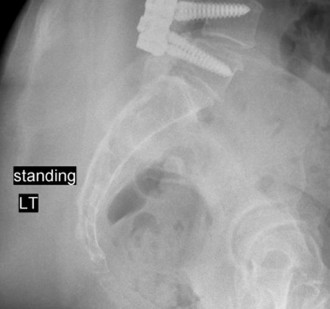

The inadequacy of modern surgical techniques to reduce or eliminate adjacent segment degeneration? CASE 16 A 51-year-old fireman whose primary complaint was chronic low back pain and right-sided leg pain underwent an L4–5 lumbar laminectomy and posterior instrumented spinal fusion for a diagnosis of L4–5 lumbar stenosis and degenerative spondylolisthesis. During surgery, bilateral pedicle screw instrumentation is placed at the L4 and L5 levels. There were no apparent complications and intraoperative radiographs including anteroposterior and lateral views were unremarkable. Immediately following surgery, the patient reported substantial relief of his right lower extremity pain, numbness, and weakness but now has difficulty sitting and walking due to new onset of severe left lower extremity pain, numbness, and weakness. Physical examination reveals a positive straight leg

raise test on the left side, dense numbness in the left great toe, and new focal weakness in left ankle and great toe dorsiflexion.

The correct answer is (D). The patient has new severe postoperative sciatica and a new neurological deficit, so simple observation is not appropriate. Intraoperative radiographs revealed no apparent abnormalities, so repeated plain radiographs are unlikely to provide additional useful information. An MRI study would be indicated if the concern was for a potential postoperative epidural hematoma, but with complete relief of pain and symptoms in one lower extremity, a hematoma becomes less likely. The most likely etiology is direct nerve root impingement from a malpositioned pedicle screw. A CT scan with sagittal and coronal reconstructions is most likely to identify this problem.

Imaging of this patient shows an inferomedial left L5 pedicle breach and likely impingement of the adjacent nerve root by the pedicle screw. What is the next most appropriate step in managing this patient?